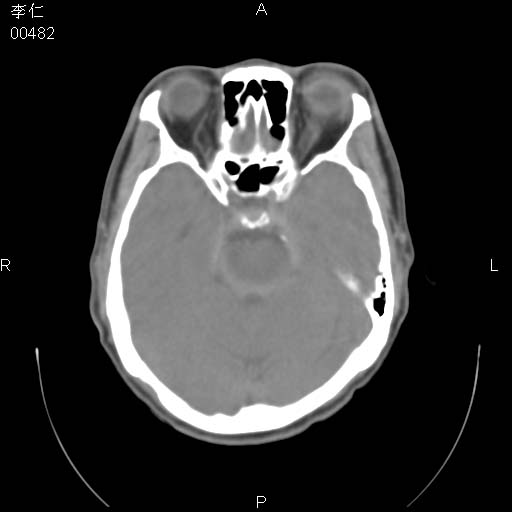

患者男,45岁。于二月前发现左眼稍肿,去看眼科,查肾功(—),来查ct,我看到的是左侧上眼睑内低密度影,ct值是-600到-700hu。

是一个副鼻窦的正常变异,脂肪瘤的密度不可能这么低,-600到-700.

只是空气而已,属正常ct表现。

正常表现,眼睑与结膜zhi间的空气

正常,为结膜囊内气体。

左侧眼球壁光滑,未见异常密度灶,眶内结构清晰,眼内肌、视神经均正常。所见低密度灶,本人考虑:1、五官科翻上睑造成;2、炎症(产气细菌感染)。